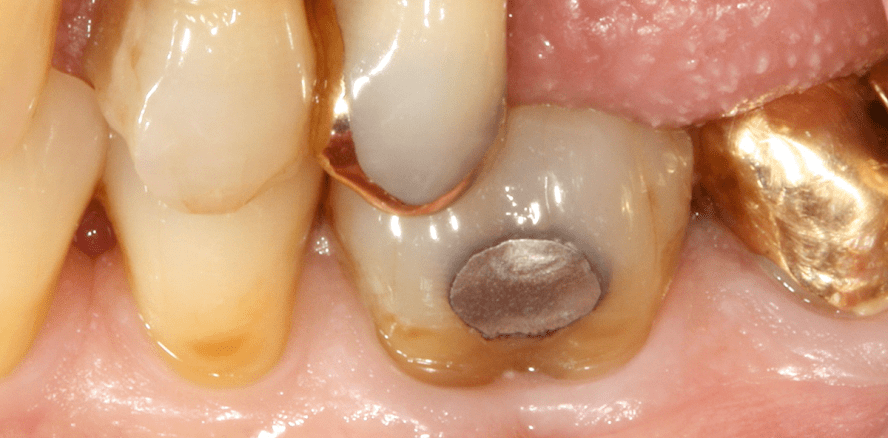

Die Messung der Furkationsbeteiligung ist ein wesentlicher Bestandteil des Attachmentstatus und für die Prognoseeinschätzung sowie die Therapieoptionen des jeweiligen Zahns von großer Bedeutung. Dies gestaltet sich allerdings nicht immer einfach, da in Abhängigkeit von der Wurzelkonfiguration und Zahnstellung nur schwer im Approximalbereich zu sondieren ist. Um dem gekrümmten Verlauf der Furkation folgen zu können, wird eine gebogene Sonde verwendet (Abb. 1). Die Einteilung der Furkationsbeteiligung richtet sich danach, wie tief die Sonde in die Furkation eindringen kann, und teilt sich in vier Grade ein (Hamp, Nyman et al. 1975) (Tab. 1). Um den interradikulären Knochenabbau noch exakter beurteilen zu können, kann die Anfertigung einer Einzelzahnröntgenaufnahme eine optimale Ergänzung darstellen. In diesem Zusammenhang ist der sogenannte Furcation Arrow von diagnostischem Wert.

Dabei handelt es sich um eine dreieckige radiologische Struktur im interradikulären Bereich, die ein Indikator für das Vorhandensein einer Furkationsbeteiligung des Grades II oder III ist (Abb. 2). Ein Fehlen dieses Furcation Arrows bedeutet im Umkehrschluss allerdings nicht, dass kein interradikulärer Knochenabbau vorhanden ist (Hardekopf, Dunlap et al. 1987). Als weiterführende radiologische Diagnostik kann zum zusätzlichen Informationsgewinn die Anfertigung eines digitalen Volumentomogramms in Betracht gezogen werden. Hier kann die dreidimensionale Darstellung des interradikulären Knochens ziemlich exakt gezeigt werden (Walter, Weiger et al. 2010). Allerdings sollte dabei die zusätzliche Strahlenbelastung der Patienten berücksichtigt werden. Daher kann die Anfertigung eines digitalen Volumentomogramms zur ausschließlichen parodontalen Diagnostik nicht uneingeschränkt empfohlen werden.